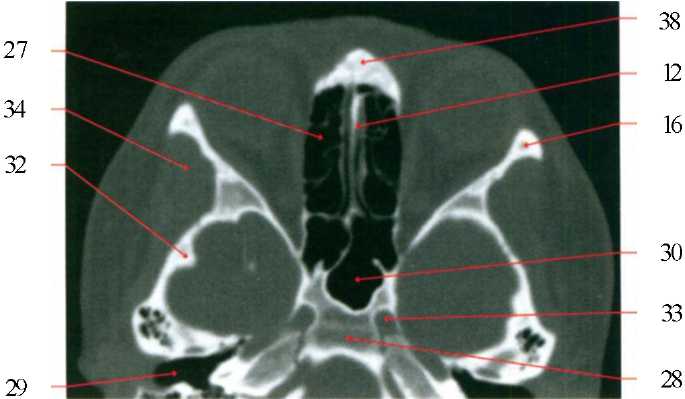

7) клиновидная (основная) пазуха; 9) решетчатый лабиринт; 10) глазное яблоко; 13) скат; 16) височная мышца; 17) мисочная доля; l8) пирамида височной кости; 23) медиальная прямая мышца; 24) полуостистая мышца головы; 25) верхняя косая мышца; 28) варолиев мост; 24) червь мозжечка; 30) затылочный синус; 31) затылочная кость; 33) лобная пазуха; 35) базилярная артерия; 36) зрительный нерв.

7) клиновидная (основная) пазуха; 13) скат; 16) височная мышца; 18) пирамида височной кости; 19) чешуя височной кости; 21) верхняя прямая мышца; 24) полуостистая мышца головы; 26) правое полушарие мозжечка; 28) варолиев мост; 29) червь мозжечка; 30) затылочный синус; 31) затылочная кость; 32) лобная кость; 33) лобная пазуха; 35) базилярная артерия; 38) средняя височная извилина; 39) нижняя височная извилина; 40) прямая извилина; 42) IV-й желудочек; 43) петушиный гребень.